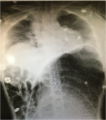

Acute gastric dilation

| current | 03:27, 12 January 2017 | ![]() | 502 × 568 (483 KB) | Mackeym2 (Talk | contribs) | Acute gastric dilation |